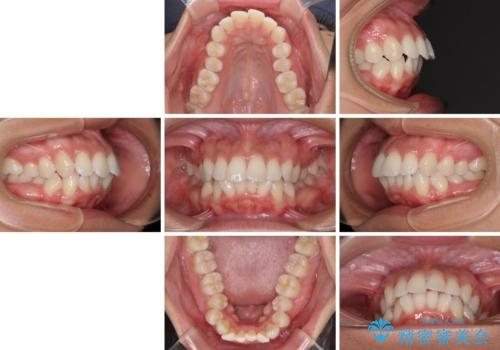

- 下唇が突き出るような口元の突出感が気になるとのことで来院された患者様です。

上下顎ともに前突した歯列であったので、上下ともに左右の第1小臼歯4本を抜歯し、ワイヤー装置にて矯正治療を行うこととしました。

抜歯スペースに前歯を移動させることで歯の突出感が改善され、非常に唇が閉じやすい仕上がりとなりました。